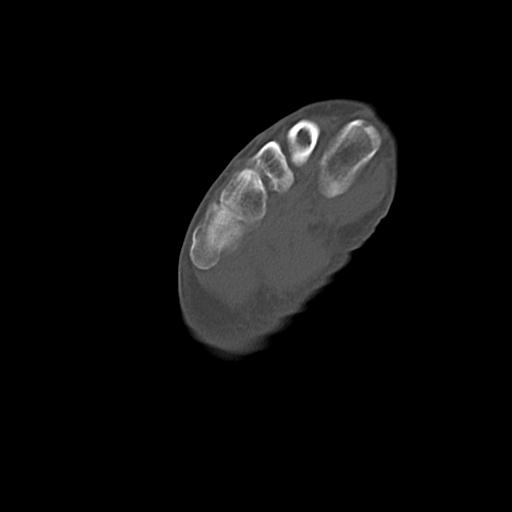

49554 3/13 膝 4R 3/16 4R 1/18 2R 78歳男性 膝蓋骨骨折